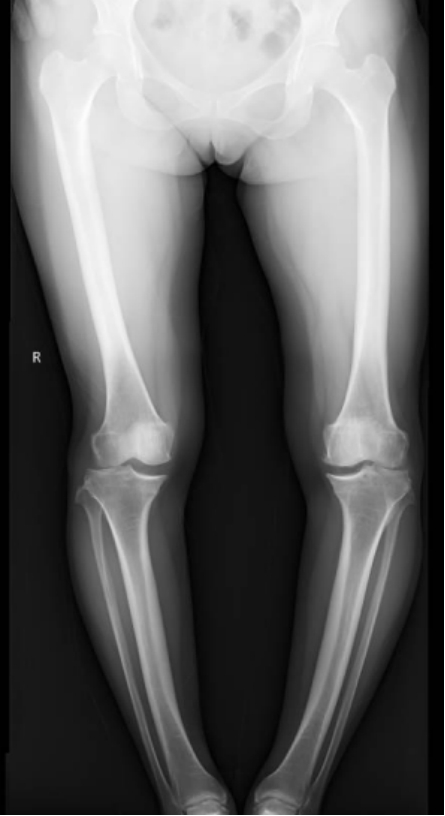

李彬在詳細(xì)了解了董阿姨的病史、進(jìn)行了全面的體格檢查和相關(guān)的輔助檢查后,組織科室進(jìn)行了深入的討論。最終的“答案”是——雙膝骨性關(guān)節(jié)炎、雙膝關(guān)節(jié)畸形、骨質(zhì)疏松以及雙膝半月板損傷。

手術(shù)前 手術(shù)后